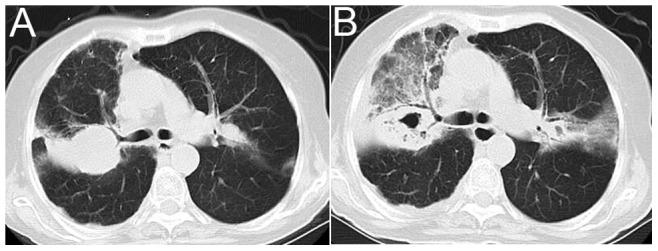

The study included 17 patients who were diagnosed with PN. Of these patients, 4 developed concomitant disseminated disease. A male predominance was observed among the patients with PN (76.47%). The most common risk factors were corticosteroid therapy (64.71%), diabetes mellitus (29.41) and chronic lung disease (23.53%). Cough and fever were the most common symptoms (94% and 71%, respectively). One or more nodules or masses (82.35%) and consolidations (58.82%) were the most frequent radiologic abnormalities, and cavitation mostly occurred within two weeks. The median time to diagnosis was 25 days. Overall, the mortality rate was 18.75% for PN, and death was most frequent among patients who received immunosuppressive drugs. For the patients with central nervous system involvement, the mortality rate was 50%.

PN remains a rare opportunistic infection that mainly affects immunocompromised patients. A high clinical index of suspicion is necessary for an early diagnosis and timely treatment in immunocompromised patients who present with new nodules or masses evolving into cavitation in a short amount of time.

本研究纳入了17例确诊为PN的患者。其中,4例并发播散性疾病。PN患者中男性占优势(76.47%)。最常见的危险因素为糖皮质激素治疗(64.71%)、糖尿病(29.41%)和慢性肺部疾病(23.53%)。咳嗽和发热是最常见的症状(分别为94%和71%)。一个或多个结节或肿块(82.35%)和实变(58.82%)是最常见的影像学异常,空洞形成大多发生在两周内。诊断的中位时间为25天。总体而言,PN的死亡率为18.75%,死亡在接受免疫抑制药物治疗的患者中最为常见。对于中枢神经系统受累的患者,死亡率为50%。

PN仍然是一种罕见的机会性感染,主要影响免疫功能低下的患者。对于出现新的结节或肿块并在短时间内发展为空洞的免疫功能低下患者,早期诊断和及时治疗需要高度的临床怀疑指数。